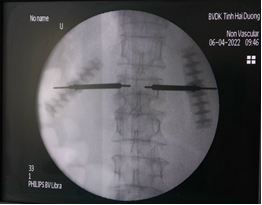

Bước 1: Xác định điểm vào thân đốt sống tổn thương thông qua cuống trên C-arm

Bước 4: Tiến hành pha trộn xi măng theo tỷ lệ để chuẩn bị bơm

Bước 5: Đây là bước quan trọng nhất khi thực hiện kỹ thuật, xi măng sinh học sẽ được bơm qua kim định vị rỗng rỗng vào thân đốt sống bị xẹp. Tốc độ bơm phải chậm và được theo dõi chặt chẽ của bác sĩ thông qua C-arm và những biểu hiện lâm sàng của bệnh nhân như tình trạng đau hay cử động hai chân.

Bước 6: Để chắc chắn xi măng sinh học chỉ khu trú trong thân đốt sống, bác sĩ sẽ kiểm tra bằng C-arm hai bình diện thêm một lần nữa.